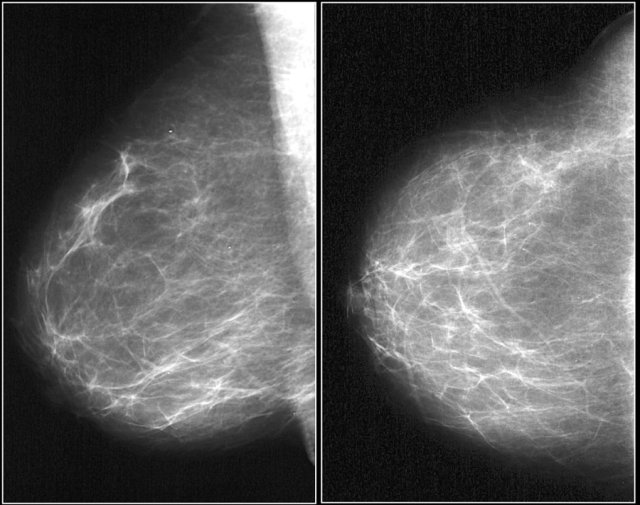

In the BI-RADS edition 2003 the assignment of the breast composition was based on the overall density resulting in ACR catergory 1 ( <25% fibroglandular tissue), category 2 ( 25-50%), category 3 (50-75%) and category 4 (>75%).

In BI-RADS 2013 the use of percentages is discouraged, because in individual cases it is more important to take into account the chance that a mass can be obscured by fibroglandular tissue than the percentage of breast density as an indicator for breast cancer risk.

In the BI-RADS edition 2013 the assignment of the breast composition is changed into a, b, c and d-categories followed by a description:

- a- The breast are almost entirely fatty.

Mammography is highly sensitive in this setting.

- b- There are scattered areas of fibroglandular density.

The term density describes the degree of x-ray attenuation of breast tissue but not discrete mammographic findings.

- c- The breasts are heterogeneously dense, which may obscure small masses.

Some areas in the breasts are sufficiently dense to obscure small masses.

- d - The breasts are extremely dense, which lowers the sensitivity of mammography.

Notice in the left example the composition is c - heterogeneously dense, although the volume of fibroglandular tissue is less than 50%.

The fibroglandular tissue in the upper part is sufficiently dense to obscure small masses.

So it is called c, because small masses can be obscured.

Historically this would have been called an ACR 2: 25-50% density.

The example on the right has more than 50% glandular tissue and is also called composition c.